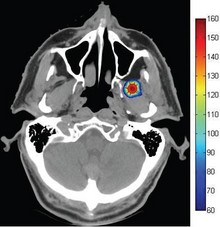

In recent years, optical manipulation using optical radiation pressure has been widely studied. In this study, the radiation pressure exerted on various kinds of microscopic objects with different laser beams was evaluated by COMSOL Multiphysics software. By changing beam shapes, ... Mehr lesen